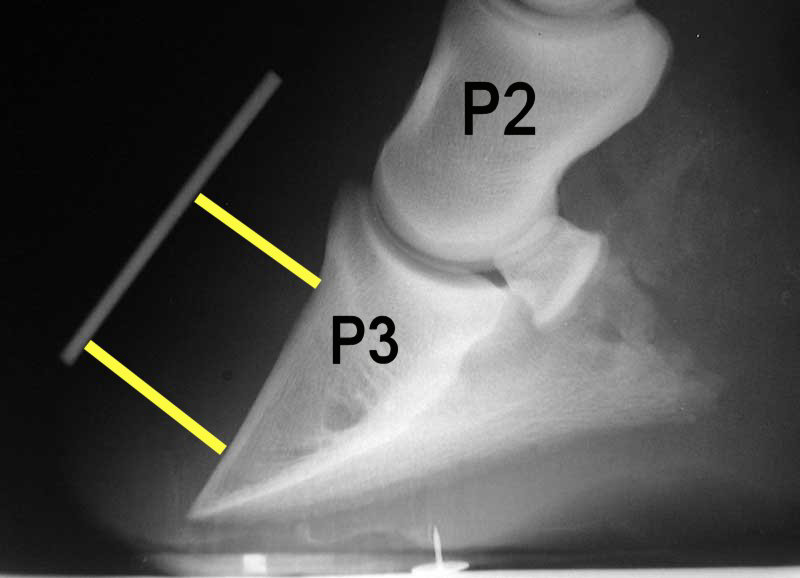

• 9yo QH, Duke presented with severe lameness and a hx of grain overload. he consumed a large amount of grain, and shortly afterwards, he became reluctant to move and displayed an abnormal posture. on CE he had an inc temp, a hard pulse in the digital arteries and he appeared in pain,(unwilling to move + hesitant gait). Tn abaxial sesamoid nerve block was performed on his forelimb digits to which effect the horse had a better range of movement and appeared much improved. The symptoms persist and after a few weeks, you take radiographs (see image). What is the diagnosis?

laminitis